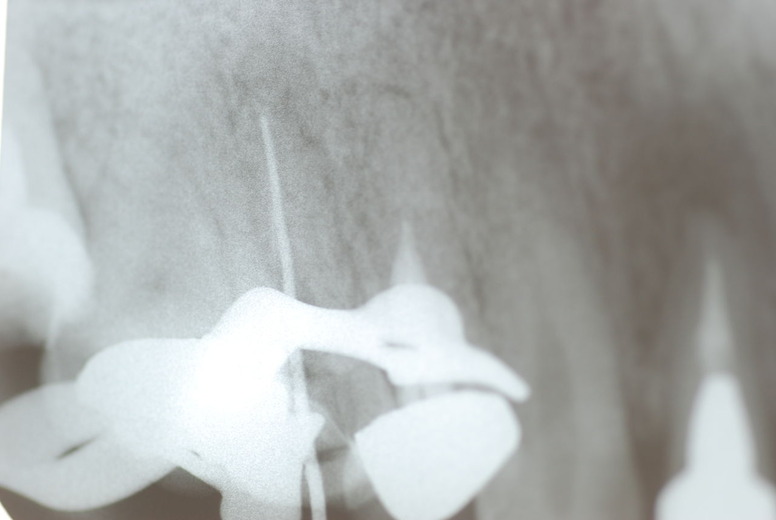

写真左下の親知らずが痛くなり抜歯しました。その後歯茎を除去して虫歯を露出させる処置を二回ほどしています。

レントゲンでは小さいですが、こう言う虫歯が一番怖いのです。

治療の成功率は極めて悪くすぐ再発しやすいのです。

隣の14歳大臼歯がひどい虫歯になり治療不可能になりつつある状態のレントゲン